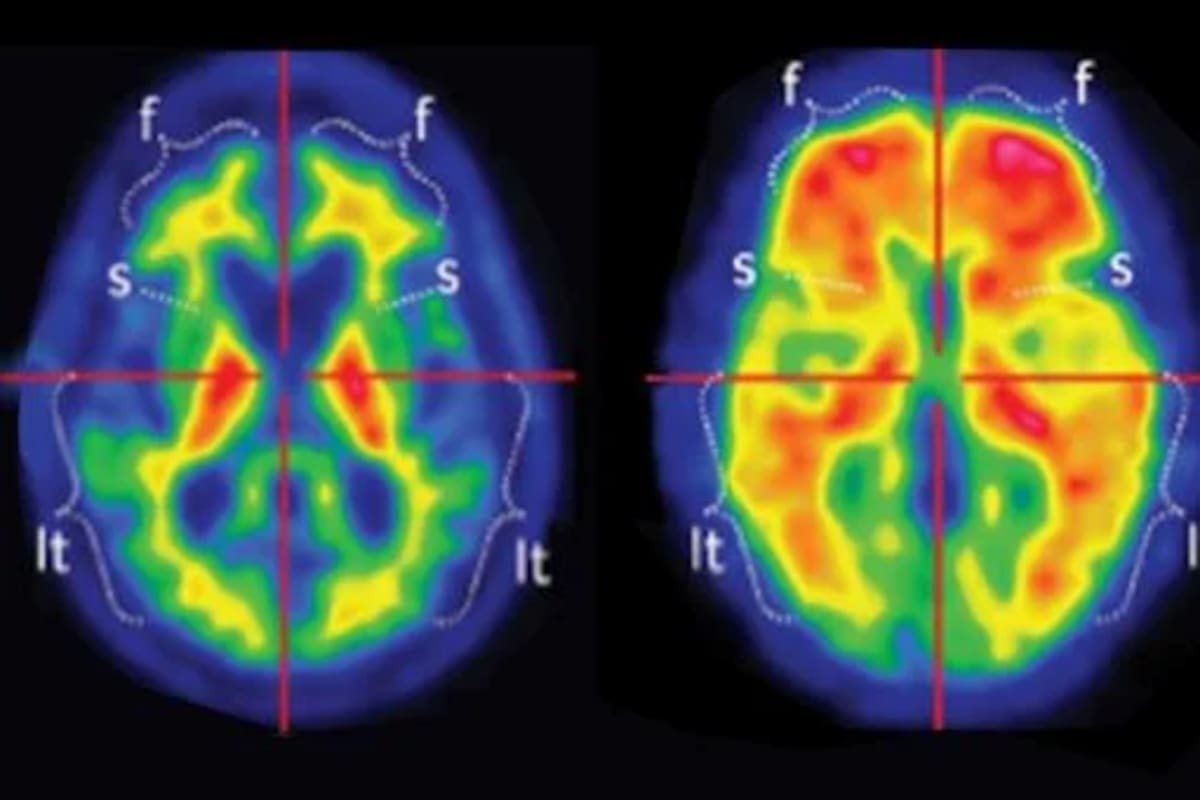

En el cerebro, el Alzheimer se caracteriza por la disfunción de dos proteínas, la beta amiloide y la tau, que forman placas y ovillos que dañan a las neuronas. Las placas amiloides pueden aparecer hasta 20 años antes de que comiencen los síntomas de demencia, mientras que los ovillos de tau aparecen más tarde, generalmente coincidiendo con el inicio del deterioro cognitivo.

Un diagnóstico de Alzheimer se basa, en parte, en la presencia de placas amiloides en el cerebro. Tradicionalmente eso se confirmaba mediante tomografías por emisión de positrones (PET) y análisis de líquido cefalorraquídeo, pero esas pruebas son costosas e invasivas, y muchos pacientes no acceden a ellas. Por eso los investigadores buscan un análisis de sangre que funcione como herramienta diagnóstica.